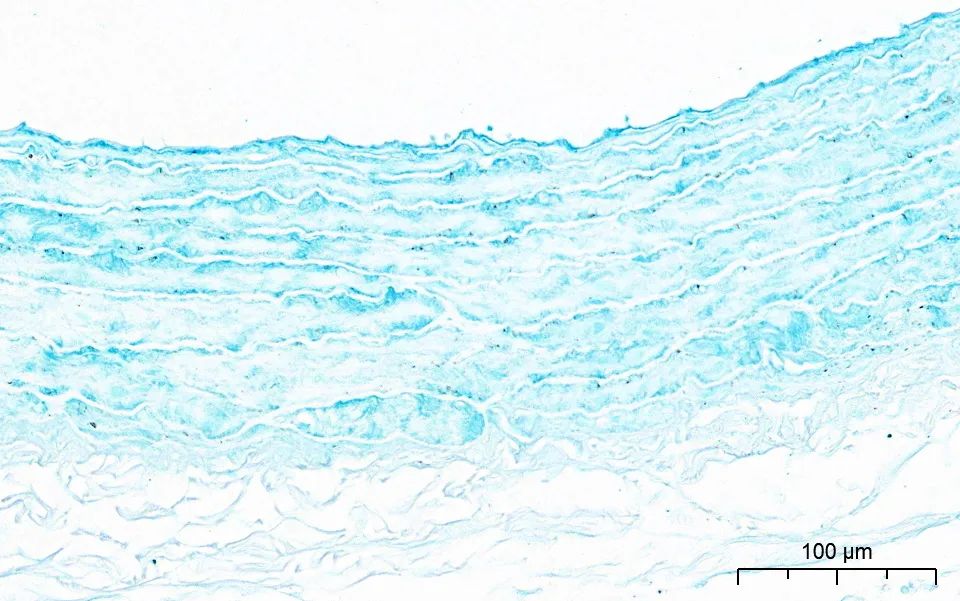

阿利新蓝染色

阿利新蓝是一种类铜钛花青共轭染料,与组织中的阴离子基团结合形成不溶性复合物。阿利新蓝由中央含铜的酞菁环和四个异硫脲基通过硫醚键相连而成,具有阳离子性质。

阿利新蓝的染色特性可通过调整染液的pH值区分粘液物质的类别。在pH值2.5时,带有负电荷的组织内羧基与阿利新蓝中的阳离子形成盐键,使带有羧基的组织(如蛋白多糖/透明质酸和上皮酸性黏蛋白)染色。

而在pH值1.0时,带有负电荷的组织内硫酸根与阿利新蓝中的阳离子形成盐键,使带有硫酸根的组织(如硫酸黏液物质)染色。

阿利新兰染色实例